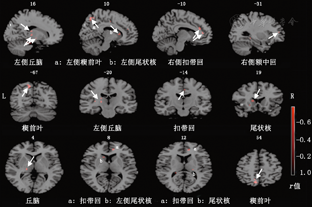

OCD患者的强迫思维与其双侧岛叶、双侧小脑、左侧距状回、左侧楔回的ReHo值呈正相关(表1、图1)。

OCD患者的强迫思维与其左侧丘脑、左侧楔前叶、左侧尾状核、右侧扣带回、右侧额中回的ReHo值负相关(表2、图2)。

| 左侧丘脑 | 0 | 16 | -22 | 6 | -0.587 15 |

| 左侧楔前叶 | 7 | 10 | -65 | 57 | -0.596 68 |

| 左侧尾状核 | 25 | 10 | 19 | 6 | -0.558 66 |

| 右侧扣带回 | 32 | -10 | 43 | 12 | -0.641 75 |

| 右侧额中回 | 46 | -31 | 48 | 13 | -0.554 23 |